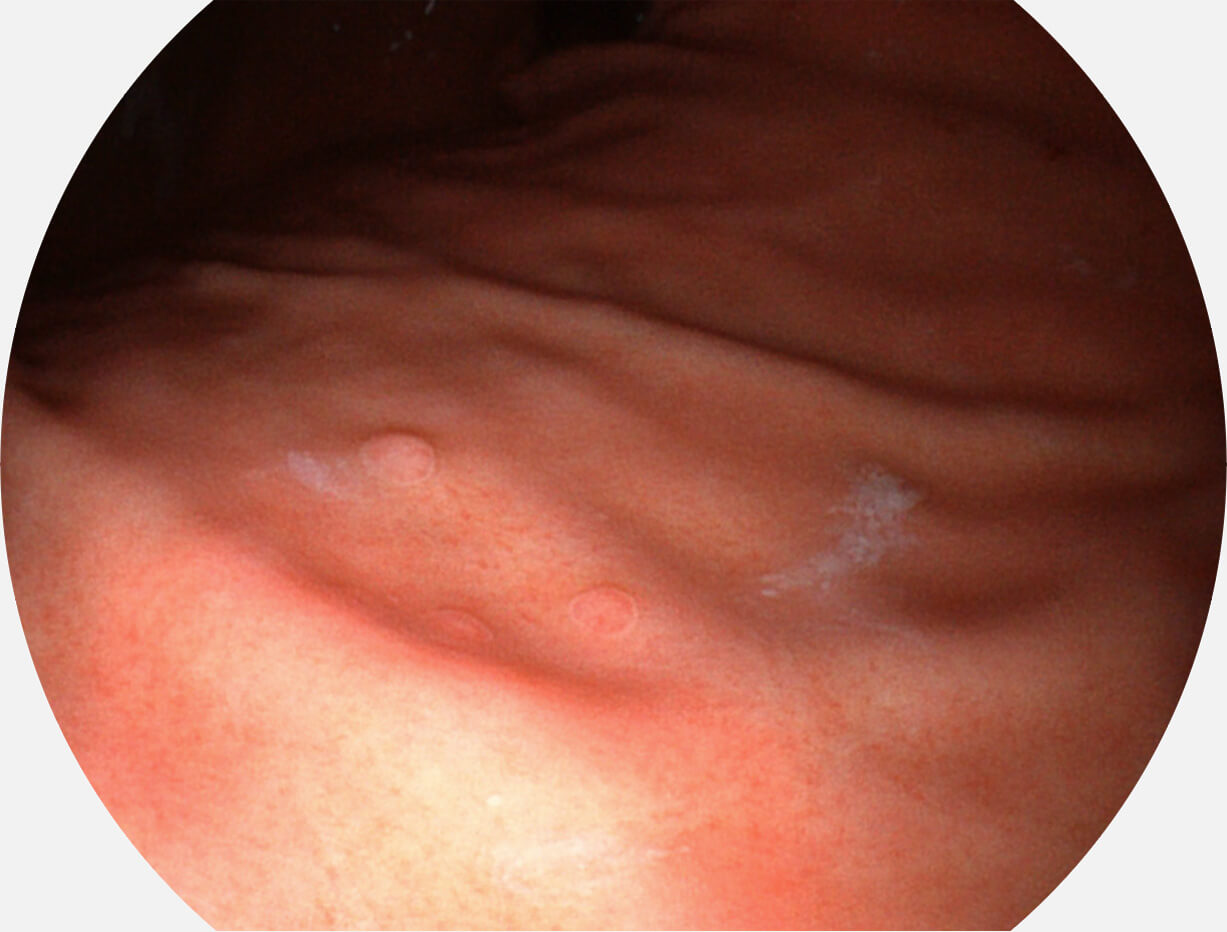

• 白光图像 SFI图像

图像具有高亮度、高黏膜血管颜色对比度的特点,且不改变粘液、食物残渣、粪便的基本颜色,可在中远景下进行观察,助力消化道早期疾病的诊断。